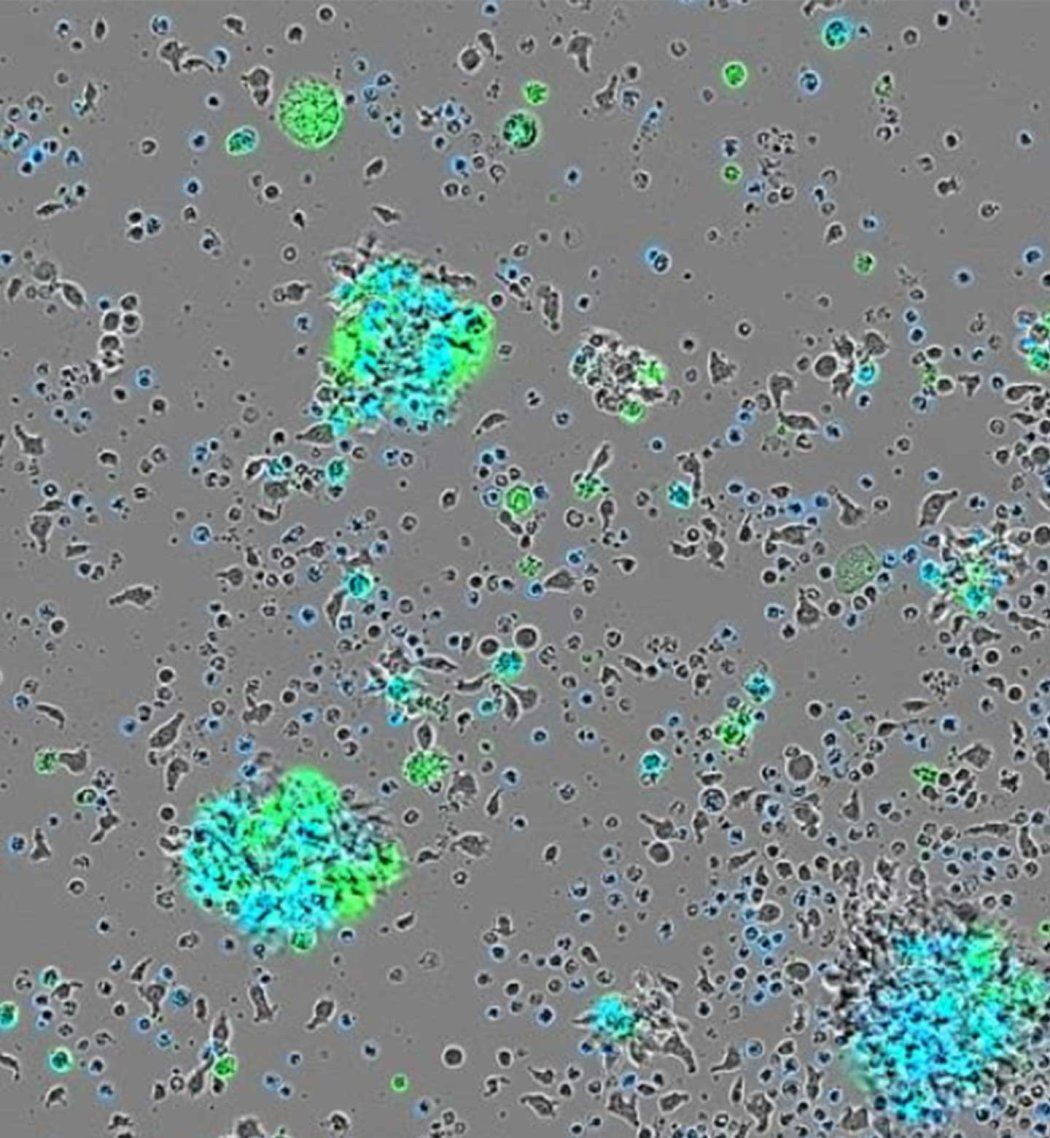

A fluorescent microscope image of cancer cells featuring blue DNA, green structural proteins, and pink SRC proteins on the cell surfaces.

The SRC protein (pink) was found on the outside of cancer cells taken from a UCSF patient. DNA is shown in blue, structural proteins outside the cells are shown in green. Credit: Corleone Delaveris, Wells Lab